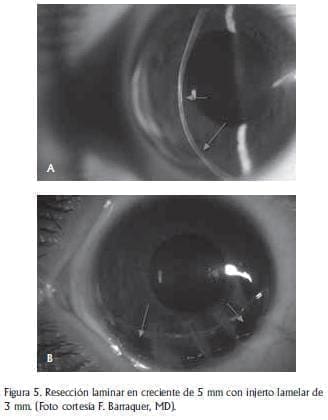

Se identificaron 3 tipos diferentes de tratamiento quirúrgico para la DMPC a saber: queratoplastia penetrante de 8.5 a 9.0 mm descentrada, resección en creciente de espesor parcial con resutura de borde a borde (técnica de Barraquer) y resección laminar en creciente de 5 mm con injerto laminar de 3 mm.

La resección semilunar de 5 mm se realizó mediante técnica ya descrita por F. Barraquer.(8,9) Se demarca con trépano de 9 mm un semicírculo yuxta-limbar inferior. Se miden 5 mm de la periferia al centro en el punto más ancho y luego se realiza una queratectomía lamelar con cuchillete de diamante “a mano alzada” de 80 a 90% de espesor. La semiluna se diseca de la misma manera que la cuña. En el ojo donante se realiza una disección similar de 3 mm de ancho. Esta es injertada en el lecho receptor y se sutura con puntos separados de Nylon 10-0 (“de colchonero”) previa paracentesis para reducir la presión intra-ocular. (Figura 5).